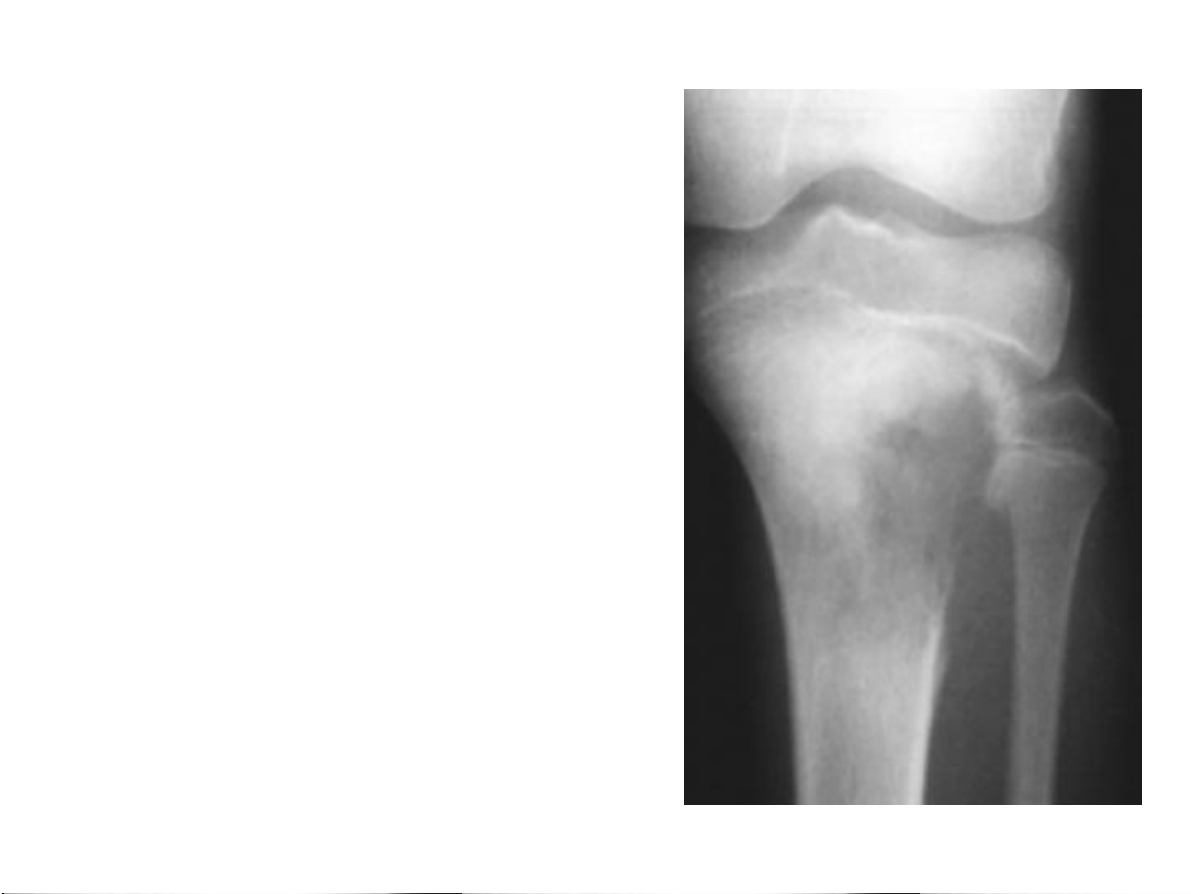

Bất thường về cấu trúc Huỷ xương 1.Giới hạn tổn thương 2.Phá huỷ vỏ xương: tổn thương ác tính? 31-Jan-23 CĐHA Cơ-Xương-Khớp

Vỏ xương: liên tục? Bị phá huỷ? Huỷ xương 1.Giới hạn tổn thương

1.Phá huỷ vỏ xương ác tính? 31-Jan-23 CĐHA Cơ-Xương-Khớp 31-Jan-23 CĐHA Cơ-Xương-Khớp 31-Jan-23 CĐHA Cơ-Xương-Khớp